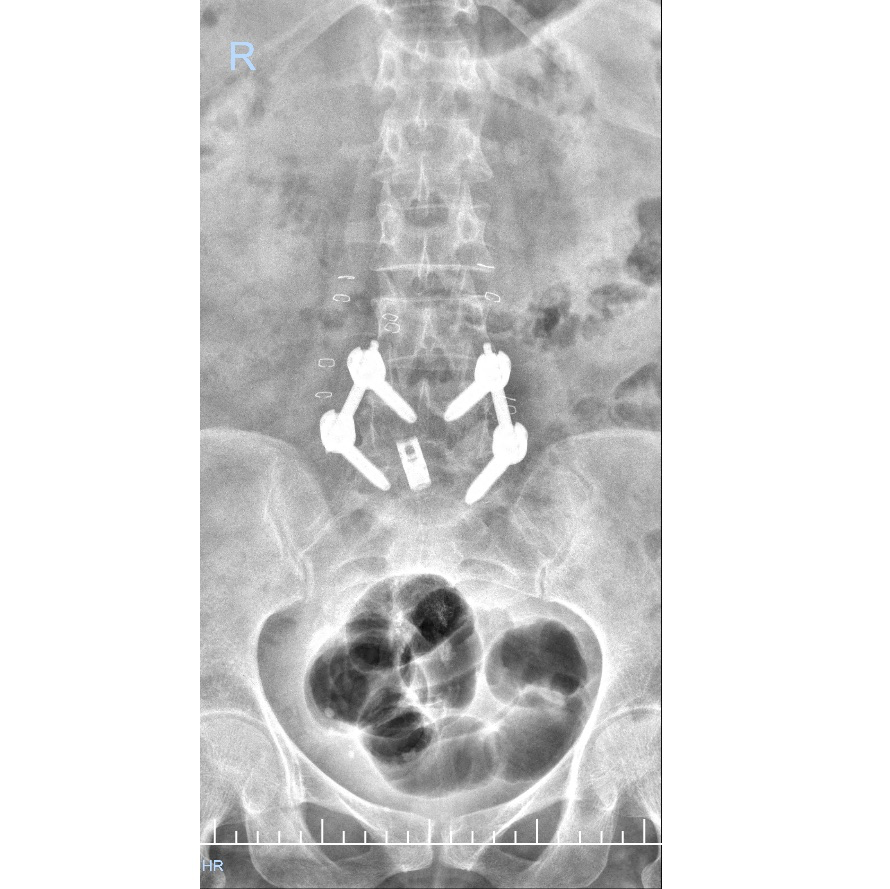

A 55-year-old lady presented with complaints of chronic low back pain with radiating leg pain for the past two years, which had significantly worsened over the last 24 hours, affecting her mobility and daily activities. Conservative management had failed to provide long-term relief. MRI of the lumbosacral spine revealed L4–L5 spondylolisthesis with disc degeneration and neural compression, consistent with her clinical symptoms. Based on detailed evaluation, she was diagnosed with L4–L5 Spondylolisthesis. The patient underwent minimally invasive endoscopic spinal fusion (Endoscopic TLIF) at Max Super Speciality Hospital, performed by Dr. Pramod Saini. The procedure was completed successfully using an advanced endoscopic technique, resulting in minimal muscle damage. The skin incision was approximately 1–2 cm, leading to reduced blood loss, less postoperative pain, and faster recovery. Post-surgery, the patient experienced significant improvement in pain and functional ability.